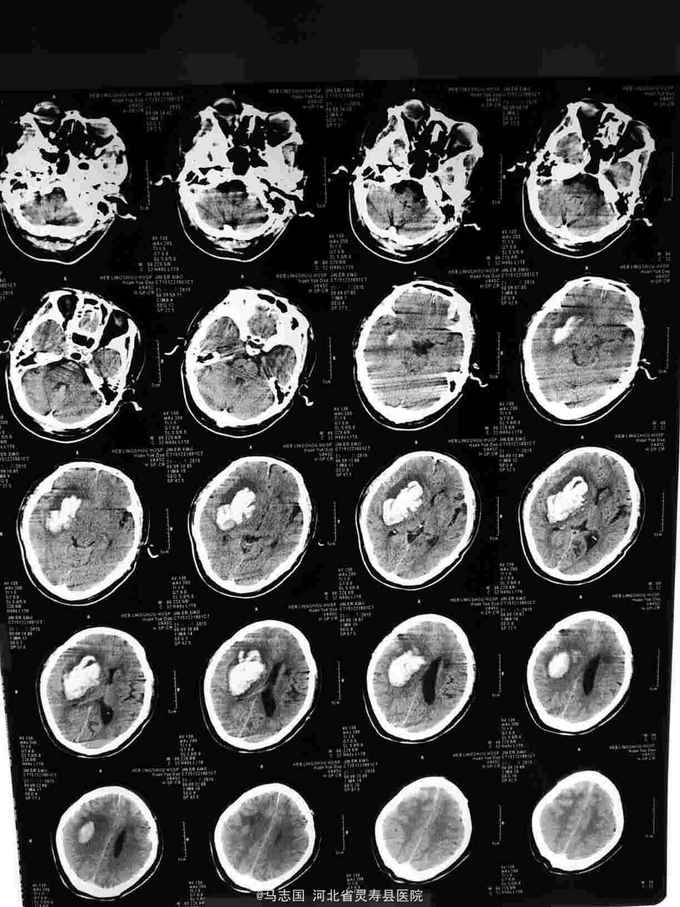

突发意识不清2小时入院,既往高血压病史,未规律服药。患者缘于2小时前劳动时,突发左侧肢体无力,烦躁不安,随即昏迷,无恶心呕吐,无肢体抽搐,无二便失禁,当地未予诊治,急打120接入院,急诊急查头CT:右侧基底节脑出血并脑疝形成,侧脑室内积血不除外,2.左额叶梗塞。为进一步诊治收住院。

1.右侧基底节脑出血并脑疝形成2.高血压3级 极高危。急诊行血肿清除,去骨瓣减压术。术后给予降颅压,促醒保护脑神经等治疗。术后第二天复查CT如下